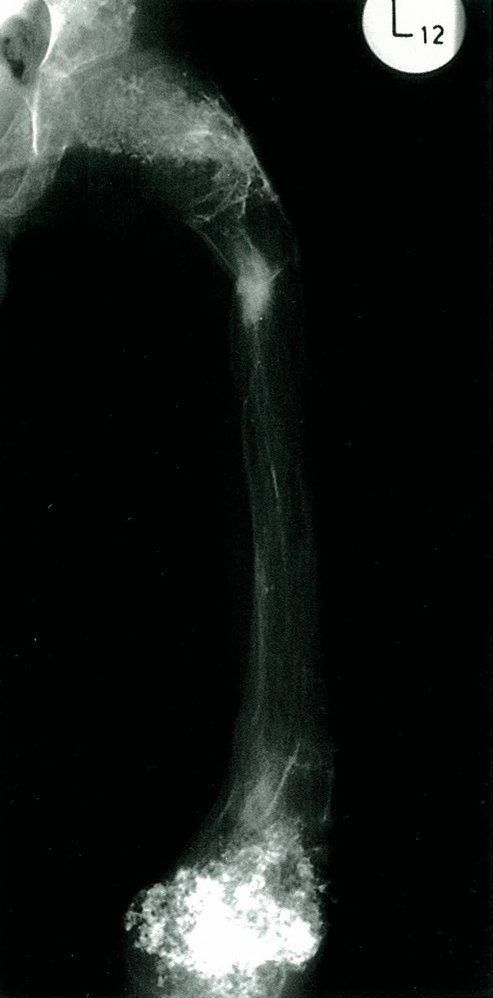

• X-ray: multicystic osteolytic lesions (soap-bubble appearance)

• Description: solitary, single-chambered cyst

• Epidemiology: peak incidence between 5 and 15 years

• Clinical features

• Found in metaphysis of the long bones (predominantly the proximal humerus and proximal femur)

• Usually asymptomatic

• Pathological fractures

• Diagnostics

• X-ray: osteolytic bone lesion with sharp margins and no sclerosis in the metaphysis of long bones

• MRI: single-chambered, fluid-filled lesion

• Treatment: monitoring or aspiration and corticosteroid injection for larger lesions

• Description

• Osteolytic lesions; usually septated, blood-filled cysts

• Idiopathic (primary aneurysmal bone cyst) or secondary to malignant or other benign bone diseases (secondary aneurysmal bone cyst)

• Epidemiology: peak incidence between 10 and 20 years

• Common sites are the spine and the metaphysis of the femur and tibia.

• Usually asymptomatic; local pain and swelling may occur

• Pathological fracture: often the first sign

• X-ray: metaphyseal, osteolytic lesion with sclerotic margins

• MRI : septated, blood-filled lesions, with typical fluid-fluid levels.

• Treatment: surgical curettage and bone grafting

• Prognosis: high risk of recurrence